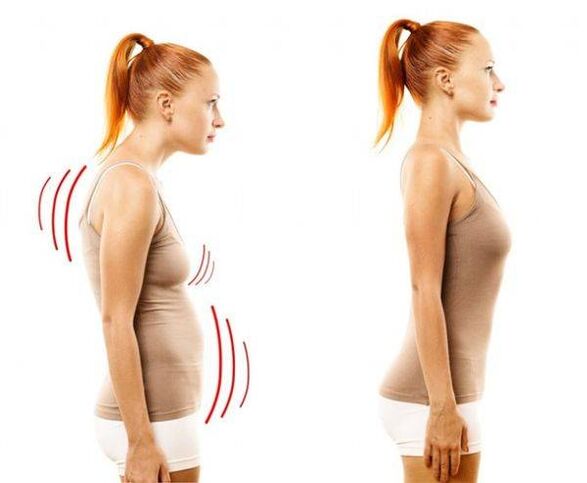

I denne sygdom bliver kernen af rygmarvsskiven tyndere og tørrer ud, det fibrøse væv omkring det begynder at forringes, og bruskvævet undergår negative ændringer. Rygsøjlen viser sig at være ude af stand til at klare normale belastninger – og det kommer primært til udtryk i udseendet af smerte, som først kommer vagt til udtryk, men med tiden bliver mere og mere intens. Men med betydelig stress - en stillesiddende livsstil, stillesiddende arbejde, konstant stress, dårlig kropsholdning og rygskader - påvirker osteochondrose før eller siden thoraxregionen. Sygdommen anses for meget almindelig - hver tredje voksen lider af den.

I de senere stadier af udviklingen af sygdommen viser smertesymptomer sig ofte i form af lumbago. Smerten er udtalt, akut, forstyrrer normal vejrtrækning, og unødvendige bevægelser forværrer kun situationen. Ofte begynder lumbago efter en længere periode med inaktivitet - for eksempel flere timers arbejde ved en computer i en statisk stilling.